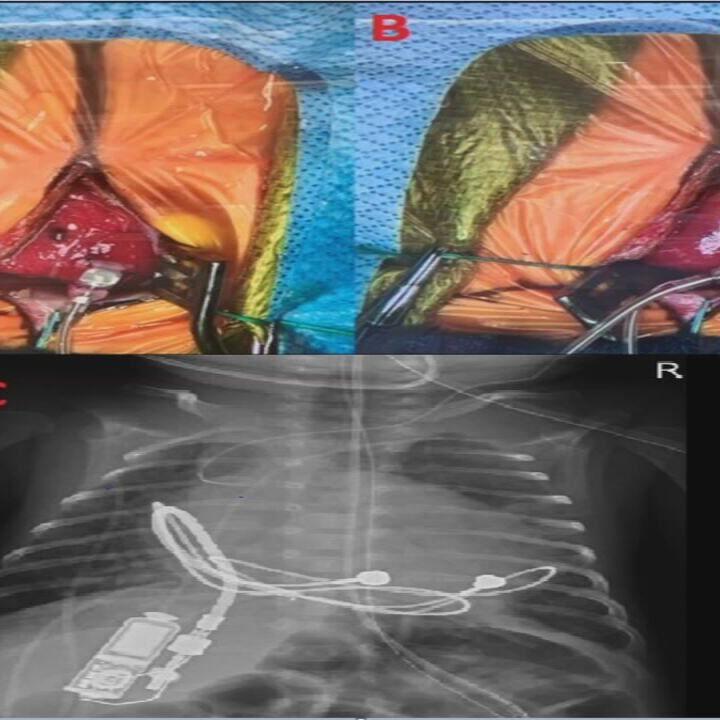

The open-heart surgery was completed in two hours, and the device measures 1.16 by 0.65 by 0.38 inches and weighs 0.18 ounces.

"While the operative steps might be comparative to the usual pacemaker implantation surgery, this surgery was especially delicate due to the very small size of the baby," Bahaaldin Alsoufi, M.D., chief of pediatric surgery and co-director of Norton Children's Heart Institute as well as a professor of cardiothoracic surgery at UofL, said in a statement. "This tiny pacemaker generator was positioned in the abdominal wall on the right side and was connected to the usual leads that were attached to the heart. This novel device will provide the necessary support that the baby currently needs. At time of repair of the patient's congenital heart defect in the future, we will be able to utilize these same leads and likely connect them to a traditional larger pacemaker generator."